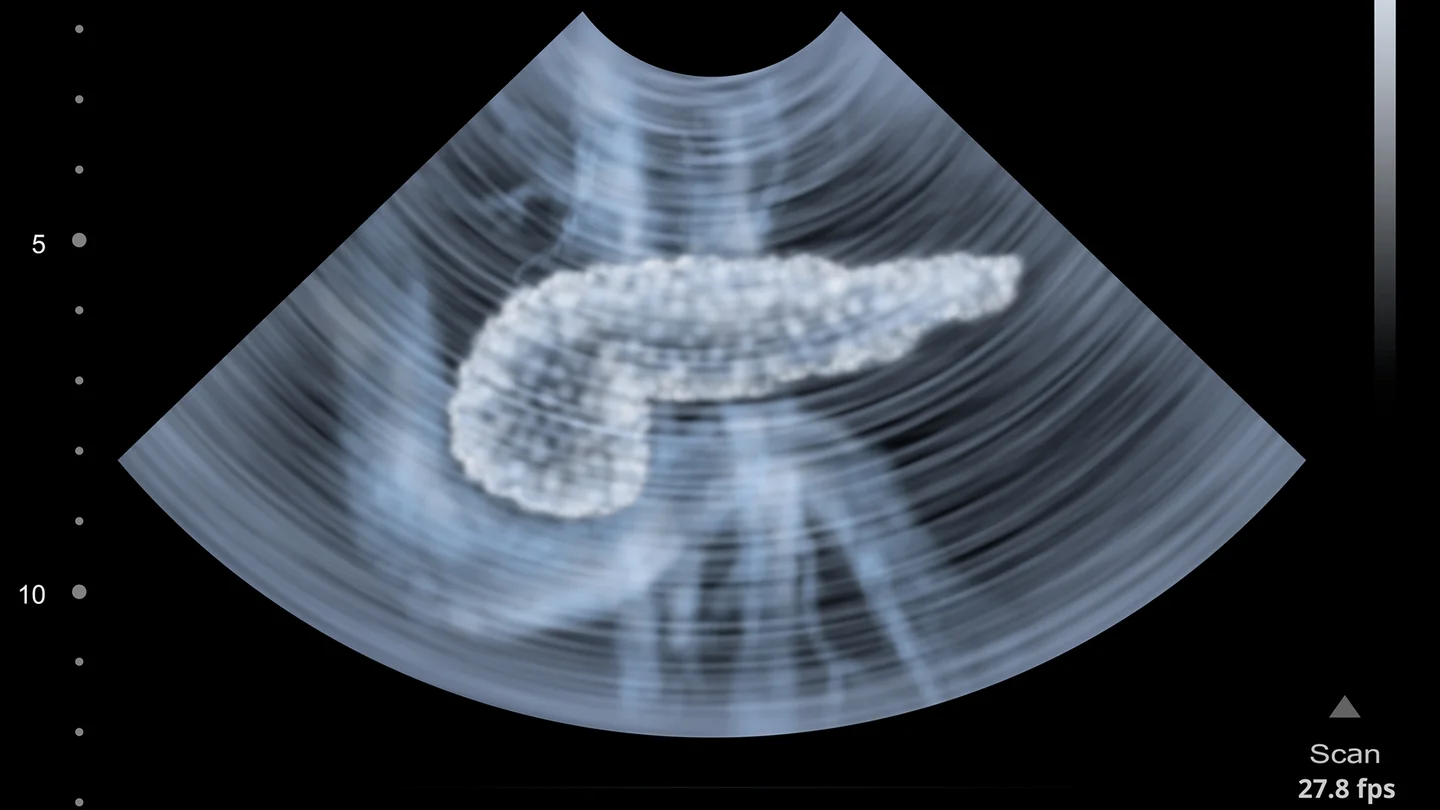

يقع البنكرياس (المعثكلة) خلف المعدة بين الطحال والاثني عشر. ويمكن تقسيمه إلى ثلاثة أقسام: الرأس والجسم والذيل.

في حالة الاشتباه في الإصابة بسرطان البنكرياس، يمكن للأطباء استخدام طرق تصوير مختلفة لتأكيد التشخيص بشكل إضافي. طرق الفحص المحتملة تشمل:

- التصوير بالموجات فوق الصوتية للجزء العلوي من البطن (تخطيط الصدى) من خلال جدار البطن،

- الموجات فوق الصوتية من الداخل (تخطيط الصدى للبطن)،